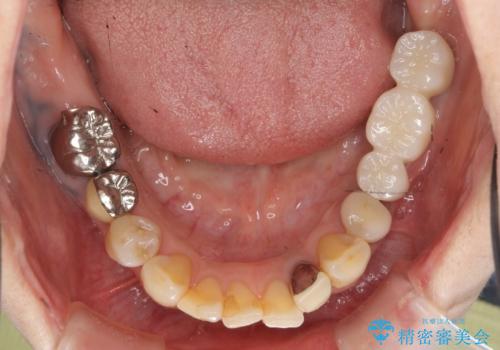

工程数が多かったため治療期間はかかりましたが、しっかりと安定した噛み合わせ、審美的な口腔内環境を達成することができ大変満足していただくことができました。